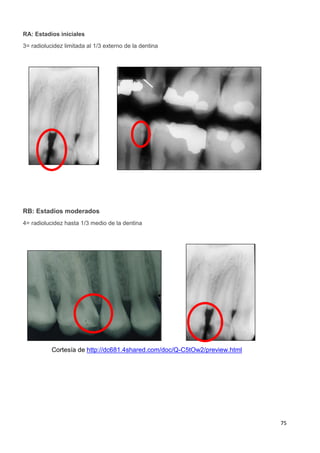

2.2.2.2 Clasificación radiográfica de las lesiones coronales de caries

La información radiográfica contribuye significativamente a los hallazgos clínicos en

términos del hallazgo de lesiones en diferentes estadíos de progresión29-32

. Las

radiografías ayudan a estimar la profundidad de desmineralización por caries en el

esmalte y la dentina. La profundidad no siempre está asociada con la presencia de

cavitación, en especial en superficies proximales.

Investigaciones clínicas que se realizaron en un país con una tasa baja de progresión de

caries revelaron que, en promedio, el 32% de las lesiones visibles radiográficamente que

se extendían hasta el tercio externo de la dentina estaban cavitadas; por el contario, el

72% de las lesiones que se extendían hasta 2/3 partes de la dentina tenían cavitación33

.

Las lesiones cavitadas clínicamente o las lesiones con obvia radiolucidez en dentina

(más profunda que el 1/3 externo) en la superficie oclusal están altamente infectadas en la

dentina más alla de la unión amelo-dentinaria34,35

Si las radiografías están disponibles, el primer paso es clasificar las lesiones de caries

coronal en dientes posteriores de acuerdo con los grados que están en la Tabla 3.

Sistema de registro ICDAS Radiográfico

Categorías

de

Caries

ICCMS™

0

Radiolucidez limitada al 1/3

externo de la dentina

RB:

Estadíos

moderados

RB 4

Radiolucidez que alcanza

hasta el 1/3 medio de la

dentina

RC:

Tabla 3. Sistema ICDAS/ICCMS™ de registro radiográfico.